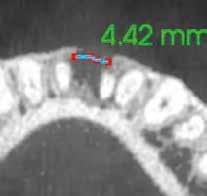

1. ábra: A 15-ös foggyökér meziális felszíne mellett látható radiolucens elváltozás, illetve a felvételen látható a korábban behelyezett gyökértömés, a parapulpális csap segítségével elhorgonyzott csonkfelépítés és a fogat borító cirkonkorona. –2. ábra: A saggitalis irányú CBCT-metszeten jól megfigyelhető az állcsontgerincet elérő radiolucens elváltozás. – 3. ábra: Az axiális irányú CBCT-metszeten egyértelműen látható a kezeletlen palatinális gyökércsatorna, valamint a radiolucens elváltozás mezio-disztális kiterjedése is jól megítélhető. – 4. ábra: A palatinális gyökércsatorna szelektív endodonciai kezelése során először gyógyszeres zárás került behelyezésre. – 5. ábra: A gyógyszeres zárás során alkalmazott kalcium-hidroxid alapú paszta a szulkuszon keresztül a szájüregbe extrudálódott. – 6. ábra: A gyökértömő anyag a középső és apikális gyökéri harmad határán lévő laterális csatornán keresztül a periapikális térbe extrudálódott. 7. ábra: A kezelések befejezését követően 4 évvel készült röntgenfelvételen jól látható a csontállomány gyógyulása és a fiziológiás gyökérhártyarés újbóli kialakulása. –8. ábra: A peroperatív CBCT-felvétel alapján készített koronális irányú metszeten jól látható a gyökércsúcs körül lévő periapikális felritkulás. – 9. ábra: A kezelések befejezése után 4 évvel készített CBCT-felvételen a gyulladásos lézió teljes megszűnése észlelhető.

A CBCT-készülékek endodonciai alkalmazásának talán az az egyik legnagyobb előnye, hogy így olyan anatómiai struktúrák is láthatóvá válnak, amelyeket egyébként nem tudnánk detektálni panoráma, cephalo, vagy periapicalis felvételek segítségével. Mivel a CBCT-felvételek kiértékelése számítógép segítségével történik, így a felvételek vizsgálata során lehetőségünk van az adott területet több nézőpontból és több síkban is megvizsgálni. 2015 októberében egy korábban a rendelőnkben kezelt 55 éves férfi páciens azzal a céllal kereste fel ismét a rendelőnket, hogy másodvéleményt kérjen egy jobb felső kvadránsban található fogával kapcsolatban. Egy másik rendelőben történő vizsgálat során a panaszos fog törését vélelmezték és a fog eltávolítását javasolták, illetve arról is beszámolt, hogy az elmúlt hét során ezen a területen egy puha duzzanat is kialakult. A klinikai vizsgálat során a jobb felső első és második kisőrlő között (14–15) egy fluktuáló duzzanatot észleltünk az áthajlásban. Az 15-ös fog mesialis oldalán 12 mm mély tasakot szondáztunk. A páciens által hozott periapicalis felvételen a 15-ös fog gyökércsúcsának mesialis részén egy nagy kiterjedésű radiolucens elváltozás volt észlelhető (1. ábra). A saggitális síkban vizsgált CBCT-felvételen (Carestream CS 9000, Carestream Dental) a lézió valódi kiterjedése is láthatóvá vált (2. ábra). A megelőző endodonciai kezelések során csupán a bukkális csatorna került detektálásra és gyökértöméssel való ellátásra. Az axiális irányú CBCT-szeleteken egyértelműen látható volt az ellátatlan palatinális gyökércsatorna (3. ábra)

Először kalcium-hidroxid alapú ideglenes gyógyszeres zárás került a palatinális csatornába (UltraCal XS, Ultradent Products; 4–5. ábra), amelyet 6 hét után a végleges gyökértömés elkészítése előtt eltávolítottunk. A gyökértömés elkészítése során meleg vertikális kondenzációs technikát alkalmaztunk. Radiológiai felvételen megfigyelhető volt, hogy a gyökértömő anyag egy laterális csatornán keresztül kis mennyiségben a periapicalis térbe extrudálódott (6. ábra). A 4 évvel később készített kontrollfelvételeken a lézió gyógyulása volt megfigyelhető (7–9. ábra). A vizsgálati eredmények és a kezelés kimenetele egyértelműen igazolta, hogy nem gyökérfraktúrával álltunk szemben, tehát a kezdeti diagnózis tévesnek bizonyult. Ez is azt erősíti, hogy korlátozott mennyiségben rendelkezésre álló adatok alapján nem lehet pontos diagnózist felállítani. Manapság szinte elengedhetetlen a CBCT-felvételek endodonciai beavatkozások során történő használata, feltéve, ha ezek elkészítése során az ALARA elv (as low as reasonably achievable) betartásra kerül.